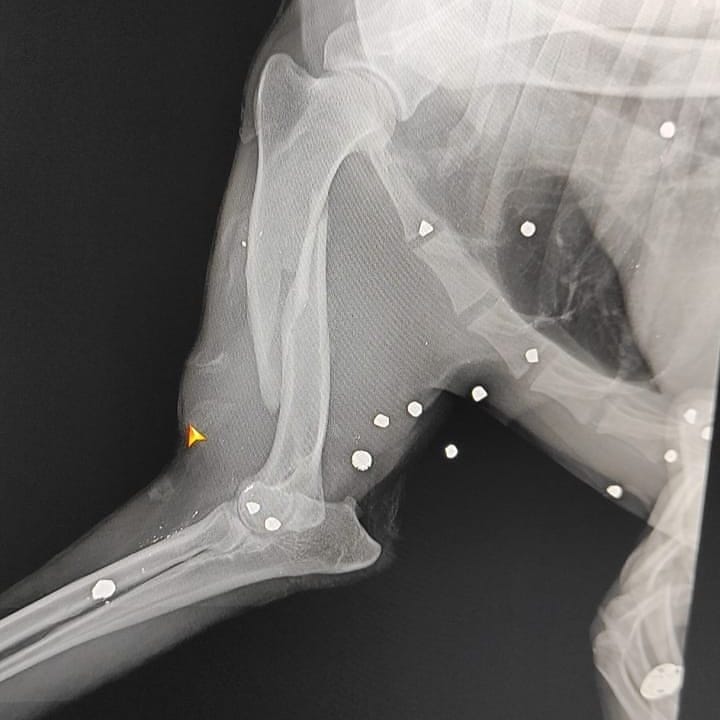

Источник фото: @mariausolАмурские зоозащитники обнаружили породистого пса с раненной лапой. Рентген показал наличие в ней пуль. Пост о случившемся появился в в соцсетях.

- Друзья, мы не знаем, как это получилось. Думали, просто поломана лапа, просто поможем и найдем хозяев, но то, что мы увидели на рентгене, поразило всех: пес буквально расстрелян в упор, - написала волонтёр. - И это только лапа, страшно подумать, что творится по всему телу, страшно представить, что он пережил!